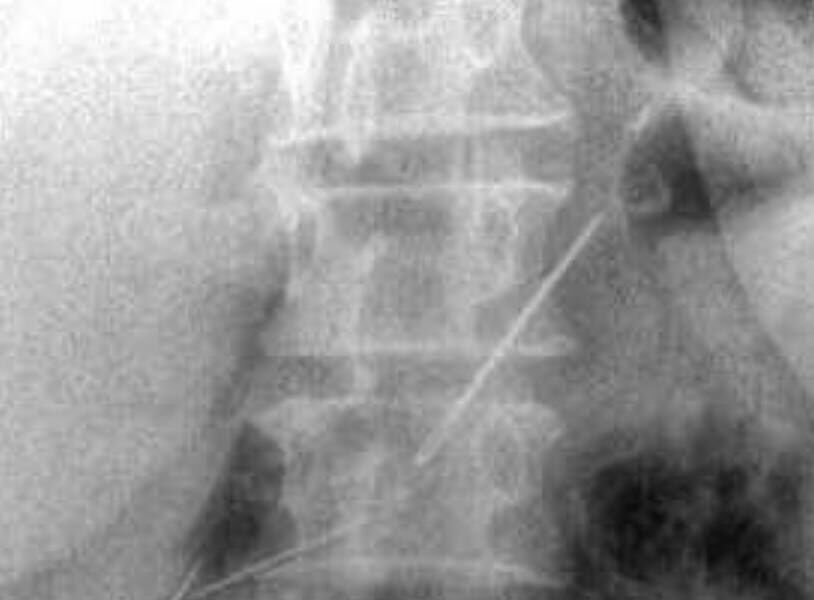

Пожилая женщина обратилась в Красногорскую больницу с жалобами на боли в животе. Пациентку обследовали и выяснили, что у нее в брюшной полости и одной передней брюшной стенке находятся четыре иглы.

Выяснилось, что женщина проглотила их около месяца назад — при каких обстоятельствах это случилось, не уточняется. За время нахождения в организме иглы успели обрасти тканями.

Медики провели пациентке лапаротомию и удалили все инородные предметы. Одна из игл проникла в поджелудочную железу, но орган все же удалось сохранить. Вмешательство прошло успешно.